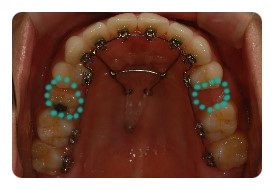

( 상악비교 )

▲ 발치 전 - 왼쪽유치 1차삭제, 오른쪽영구치 발치 예정

▲ 6월 - 스크류식립 후 본격적으로 상악당기기 1개월차

▲ 8월 - 3개월차

▲ 10월 - 5개월차

조신하지못한 저의 잦은 어금니 브라켓탈락 ㅠㅠ 에도 불구하고 잘 이동하고 잇는듯해요